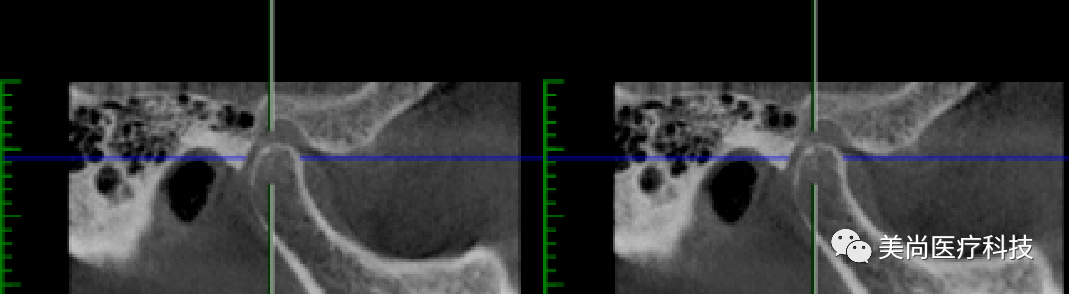

32、42可用骨宽度6mm,可用骨高度10mm;

34、44可用骨宽度6mm,可用骨高度11.5mm。

制作导板,导板引导下植入种植体

导板下植入植体:

在32、42处植入3.5*10mm植体各一颗,植入扭矩约35n.cm;

在34、44处植入4.0*11.5mm植体各一颗,植入扭矩约40n.cm。